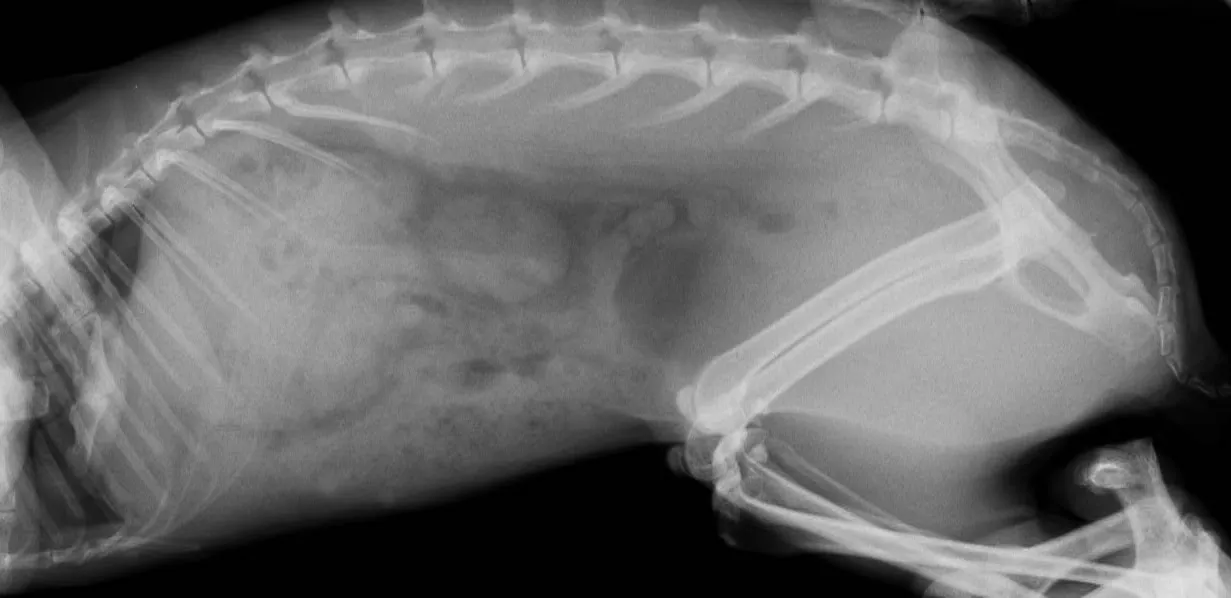

ウサギの食滞や毛球症、消化器機能不全(ウサギ消化器症候群:RGIS)の症状のことです。

胃内容、腸内容の停滞、ガス貯留、うっ滞、腸閉塞などの病態が複雑に関与して食欲不振、廃絶は起こります。

停滞が改善され、消化器の機能が回復する補助を様々行うのが治療ですが、功を奏しない場合は死亡することもあります。最近では内科的処置だけでなく、外科的処置で内容物の除去が行われるようになりましたが、ハードルは少々高めです。当院では内科的な治療の他に鍼灸治療や腹部のマッサージなどを併せて実施指導します。